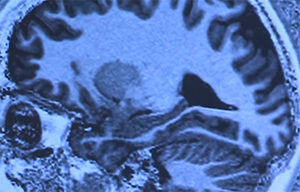

Experiências espirituais e religiosas ativam área de recompensa do cérebro

Dezenove participantes jovens e adultos foram analisados por pesquisadores durante momento religioso intenso.

Dezenove participantes jovens e adultos foram analisados por pesquisadores durante momento religioso intenso.

As experiências espirituais e religiosas ativam os circuitos de recompensa do cérebro, da mesma forma que acontece com o amor, sexo, jogos de azar, drogas e música. Os resultados são da Faculdade de Medicina da Universidade de Utah e foram publicados nesta terça-feira (29) na revista “Neuroscience social”.